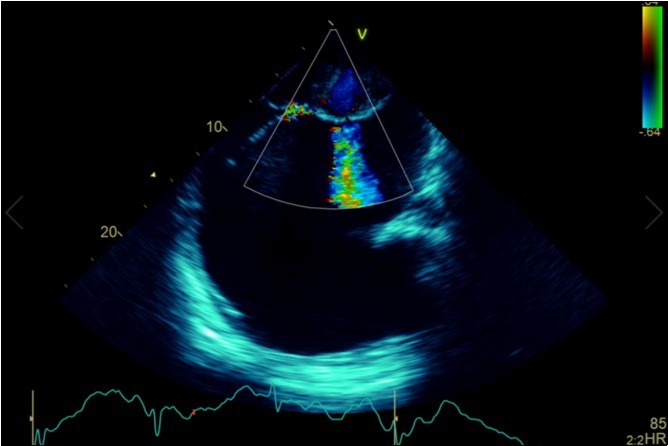

A dramatically dilated left atrium was seen on a TTE (see Figure 2a, Figure 2b, Figure 2c, and Figure 2d). Severe mitral stenosis with associated regurgitation was evident, with a mean gradient across the valve of 11mmHg and a hyperdynamic left ventricle. The left atrial volume measured by Simpson’s biplane method (see Figure 2c) was 2108mL, or 1548.5 ml/m2, based on height 1.55 metres and weight 44 Kg. Normal left atrial volume in a woman is 16 - 34 ml/m21. The computed tomography scan (CT) chest AP view (see Figure 3) is also shown.

Figure 2a.Transthoracic echocardiogram Apical 4C view. Findings include severely enlarged left atrium, severe mitral stenosis with associated regurgitation, a mean gradient across the valve of 11mmHg with a hyperdynamic left ventricle